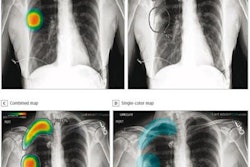

Under the terms of the deal with the Korean National IT Industry Promotion Agency, Lunit will deliver its Insight CXR software to more than 30 Korean military medical sites by the end of 2022. The software detects nine types of abnormalities via chest x-ray and aims to better detect critical lung diseases, including tuberculosis.